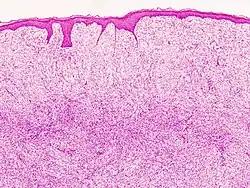

| Histopathological image of dermatofibrosarcoma protuberans. Local recurrence long after the first excision. H&E stain | |